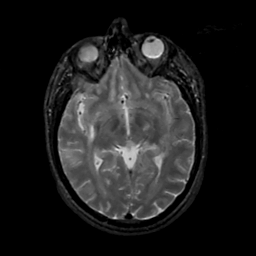

MR Study #14, June 2, 1991 -- Slice #23